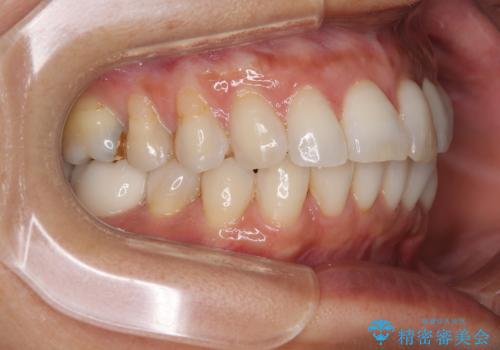

むし歯と前歯のデコボコを治したい インビザラインを使用した総合歯科治療

- 目立つ銀歯やむし歯、前歯のデコボコを気にして来院された患者様です。

デコボコはある程度改善できれば良いとのことでしたので、インビザラインの廉価版を用いて矯正治療を行うこととしました。

飛行機での通院であり、更にはご家族がの都合で海外に滞在されることも多いため、中等度の歯列不正に対応可能なインビザライン・モデレートパッケージを使用することとしました。

むし歯治療は、症状のある歯を矯正治療前に処置し、概ね歯列が整ったところで残りのは全て処置し、最後にインビザラインで歯列を仕上げることで、無駄なく治療を進めて行くこととしました。